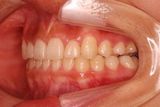

治療前 の 左 です 動く矢印治療後 の 左 です

治療前 の 右 です 動く矢印治療後 の 右 です